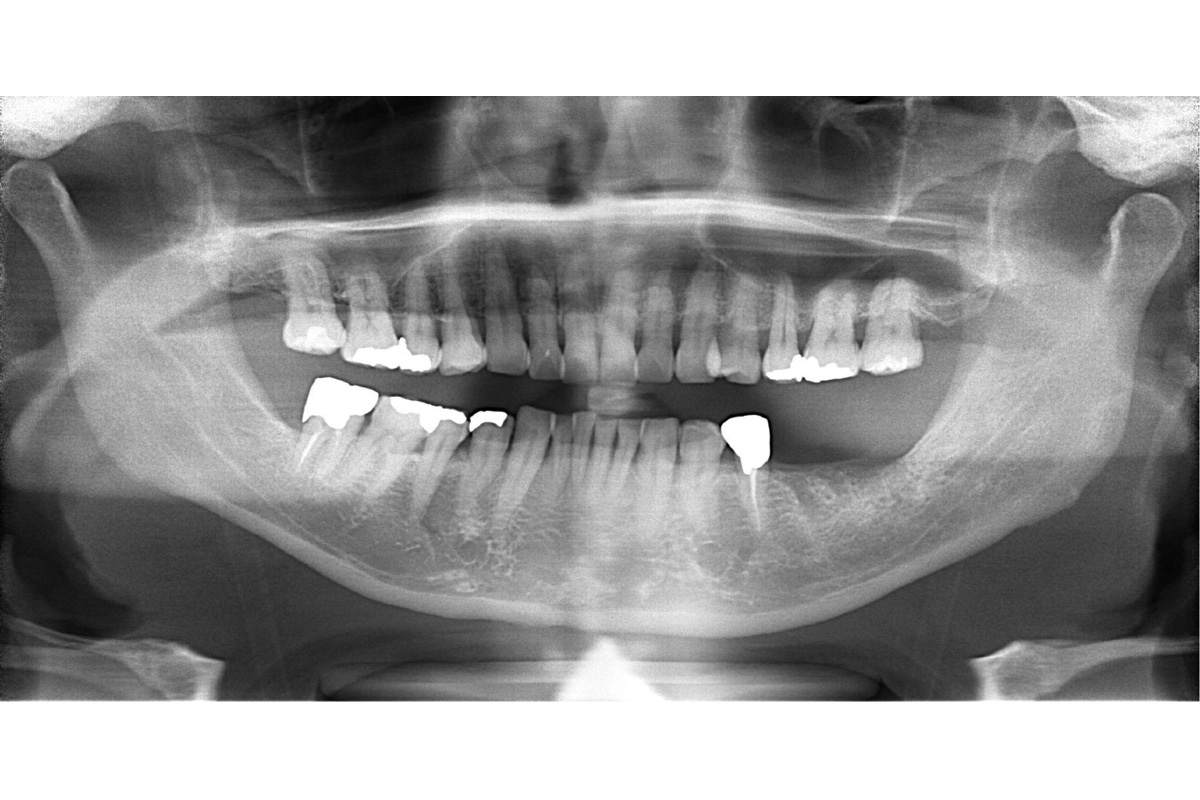

治療前

| 主訴 | 左下の奥歯を入れ歯以外で治したい |

| 治療内容 | 抜歯・骨造成 インプラント治療 |